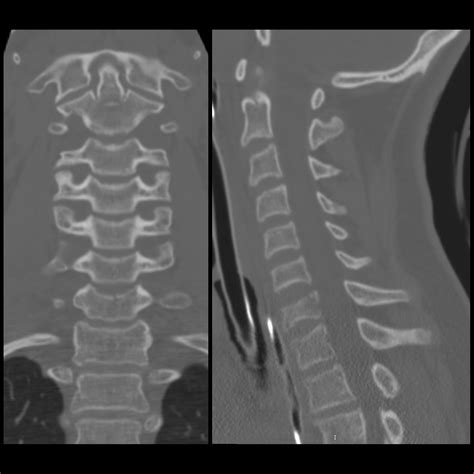

• Multiplanar Reconstruction (MPR): This technique allows for the creation of images in multiple planes (axial, sagittal, and coronal), providing a more comprehensive view of the spine.

Interpreting cervical spine CT images requires a thorough understanding of spinal anatomy and the ability to identify various pathologies. Key structures to focus on include:

• The vertebrae, which are the individual bones that make up the spine.

• The intervertebral discs, which act as cushions between the vertebrae.

• The spinal canal, which houses the spinal cord.

• The facet joints, which allow for movement between the vertebrae.